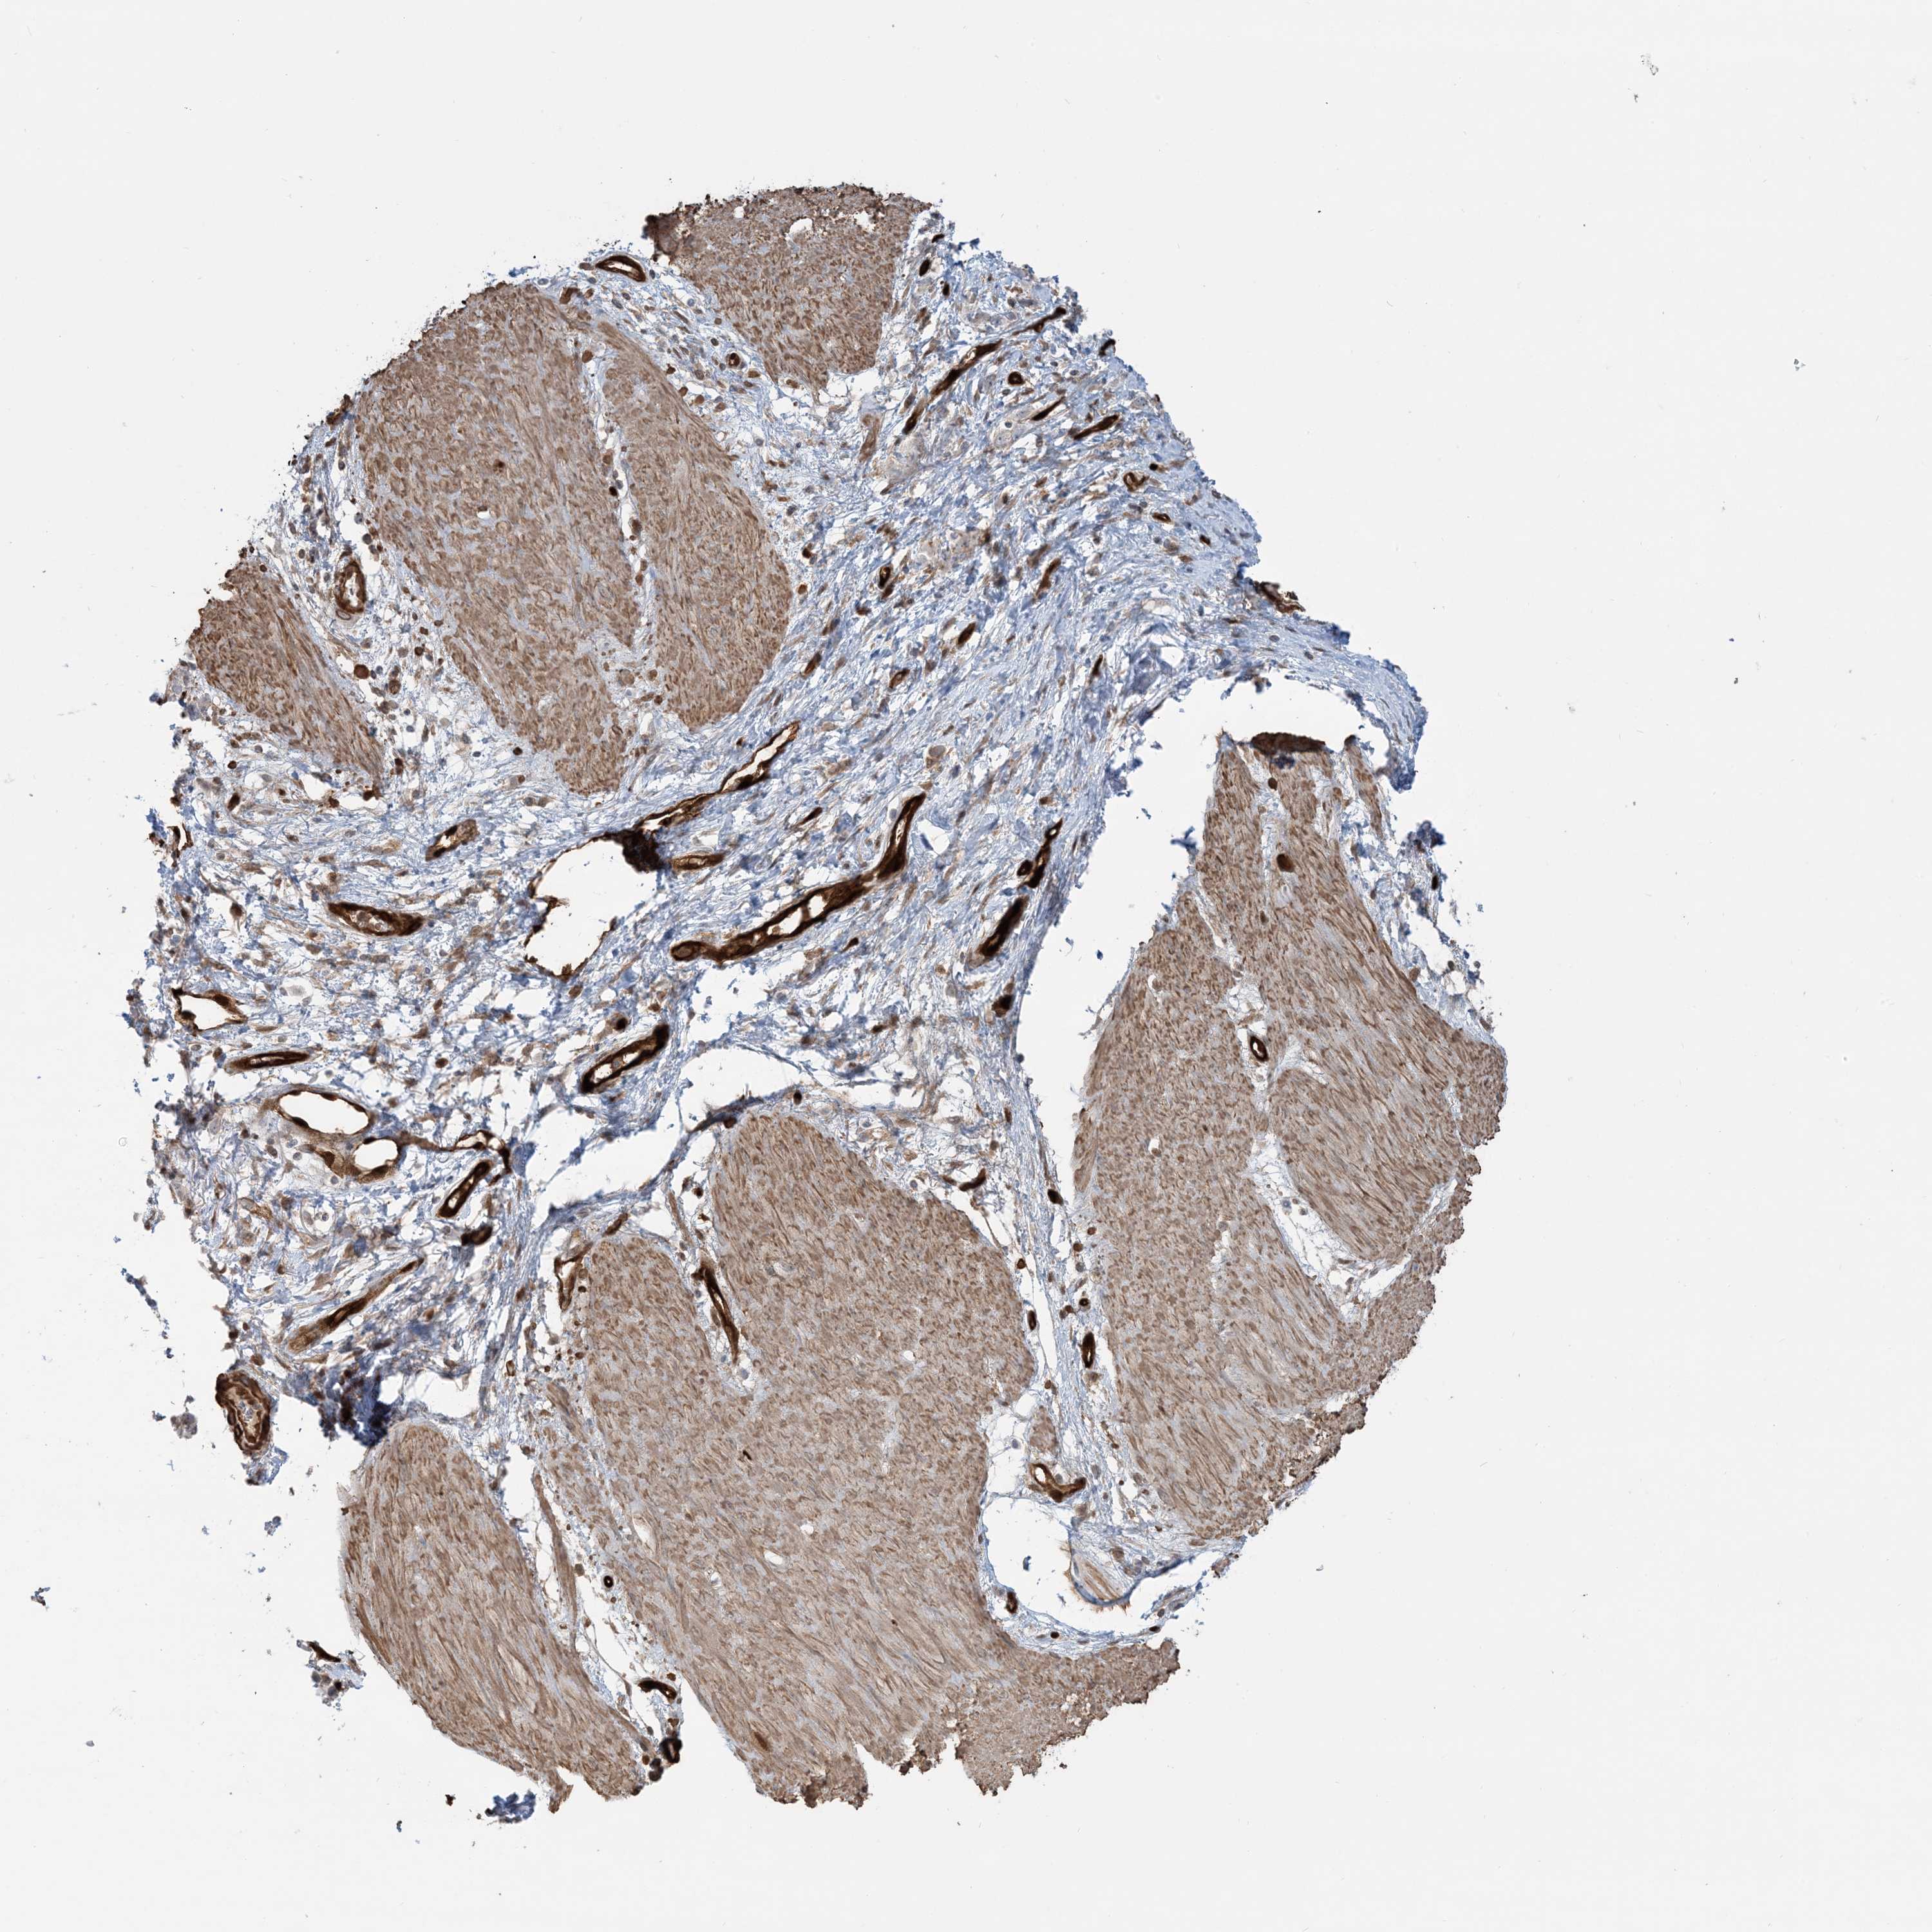

STOMACH CANCER - Protein expressioni

A mouse-over function shows sample information and annotation data. Click on an image to view it in a full screen mode. Samples can be filtered based on level of antibody staining by selecting one or several of the following categories: high, medium, low and not detected. The assay and annotation is described here.

Note that samples used for immunohistochemistry by the Human Protein Atlas do not correspond to samples in the TCGA dataset.

Antibody stainingi

Antibody staining in the annotated cell types in the current human tissue is reported as not detected, low, medium, or high, based on conventional immunohistochemistry profiling in selected tissues. This score is based on the combination of the staining intensity and fraction of stained cells.

Each image is clickable and will lead to virtual microscopy that enables deeper exploration of all samples and also displays staining intensity scores, fraction scores and subcellular localization as well as patient and tissue information for each sample.

Antibody HPA030989

Antibody HPA030990

Staining

High

Medium

Low

Not detected

Intensity

Strong

Moderate

Weak

Negative

Quantity

>75%

75%-25%

<25%

None

Location

Nuclear

Cytoplasmic/membranous

Cytoplasmic/membranous,nuclear

Adenocarcinoma, NOS